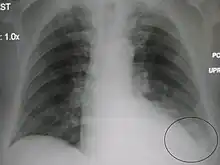

The discovery of x-rays made it possible to determine the anatomic type of pneumonia without direct examination of the lungs at autopsy and led to the development of a radiological classification. Early investigators distinguished between typical lobar pneumonia and atypical (e.g. Chlamydophila) or viral pneumonia using the location, distribution, and appearance of the opacities they saw on chest x-rays. Certain x-ray findings can be used to help predict the course of illness, although it is not possible to clearly determine the microbiologic cause of a pneumonia with x-rays alone.